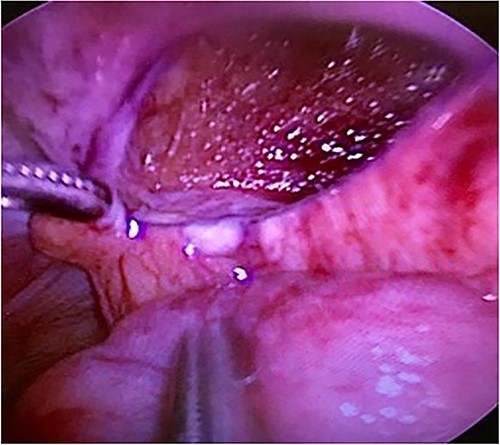

Computed tomography revealed caliber changes in the small bowel at the site of post-hernia repair in the left inguinal region (Figs 1 and 2), and the patient underwent laparoscopic surgery under general anesthesia. Intraperitoneal observation revealed that the peritoneal suture in the left inguinal region was detached, and a hole in the peritoneum had formed a hernial orifice (Fig. 4), causing SBO because of preperitoneal herniation (Fig. 3). The hernia was released, the peritoneal hole was sutured again and the surgery was completed. The postoperative course was good, and the patient was discharged from the hospital on the third postoperative day after reoperation.

The closed peritoneum was lacerated, and the small bowel was incarcerated in the preperitoneal space.